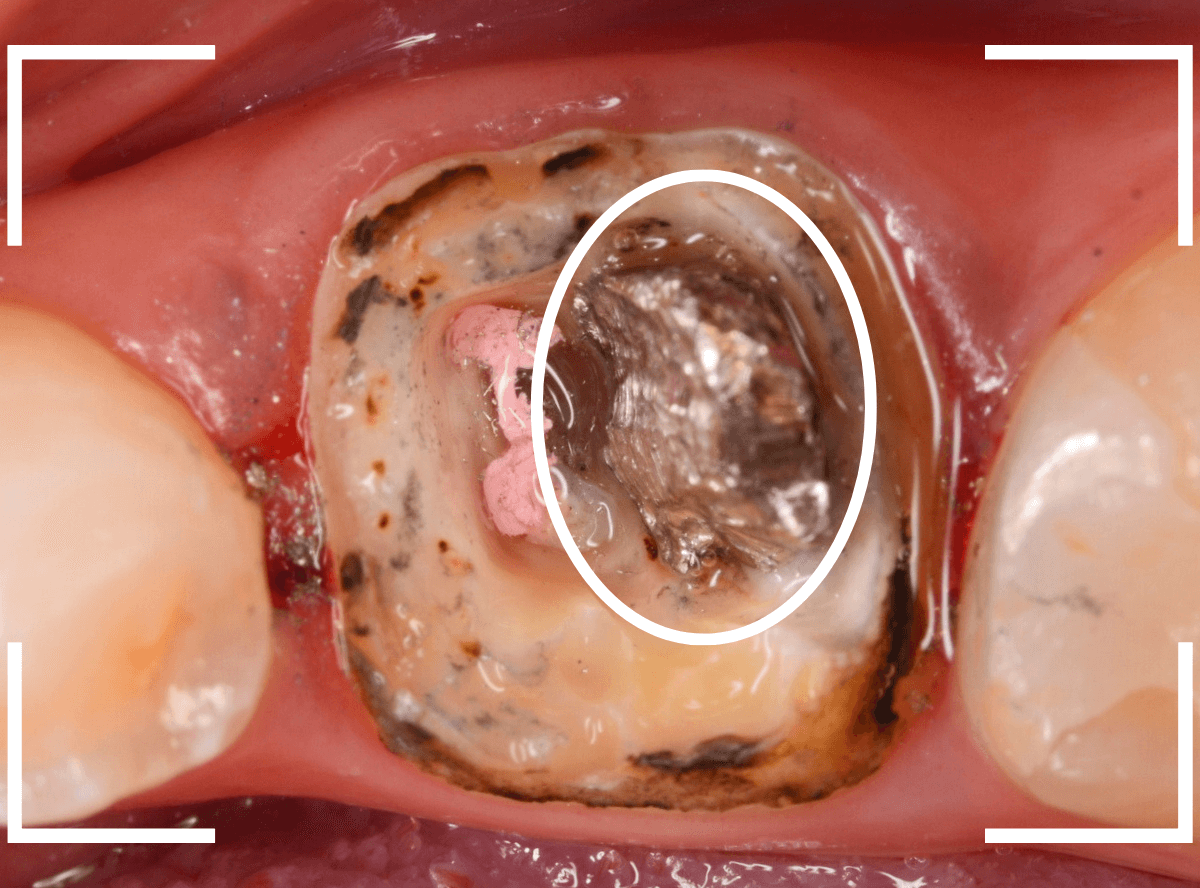

虫歯を全て除去しました。

幸い、あまり多く削る事なく進められたので良かったです。

赤く染色されている部分が虫歯の残っているです。

慎重に虫歯を除去して、土台の型を取ります。